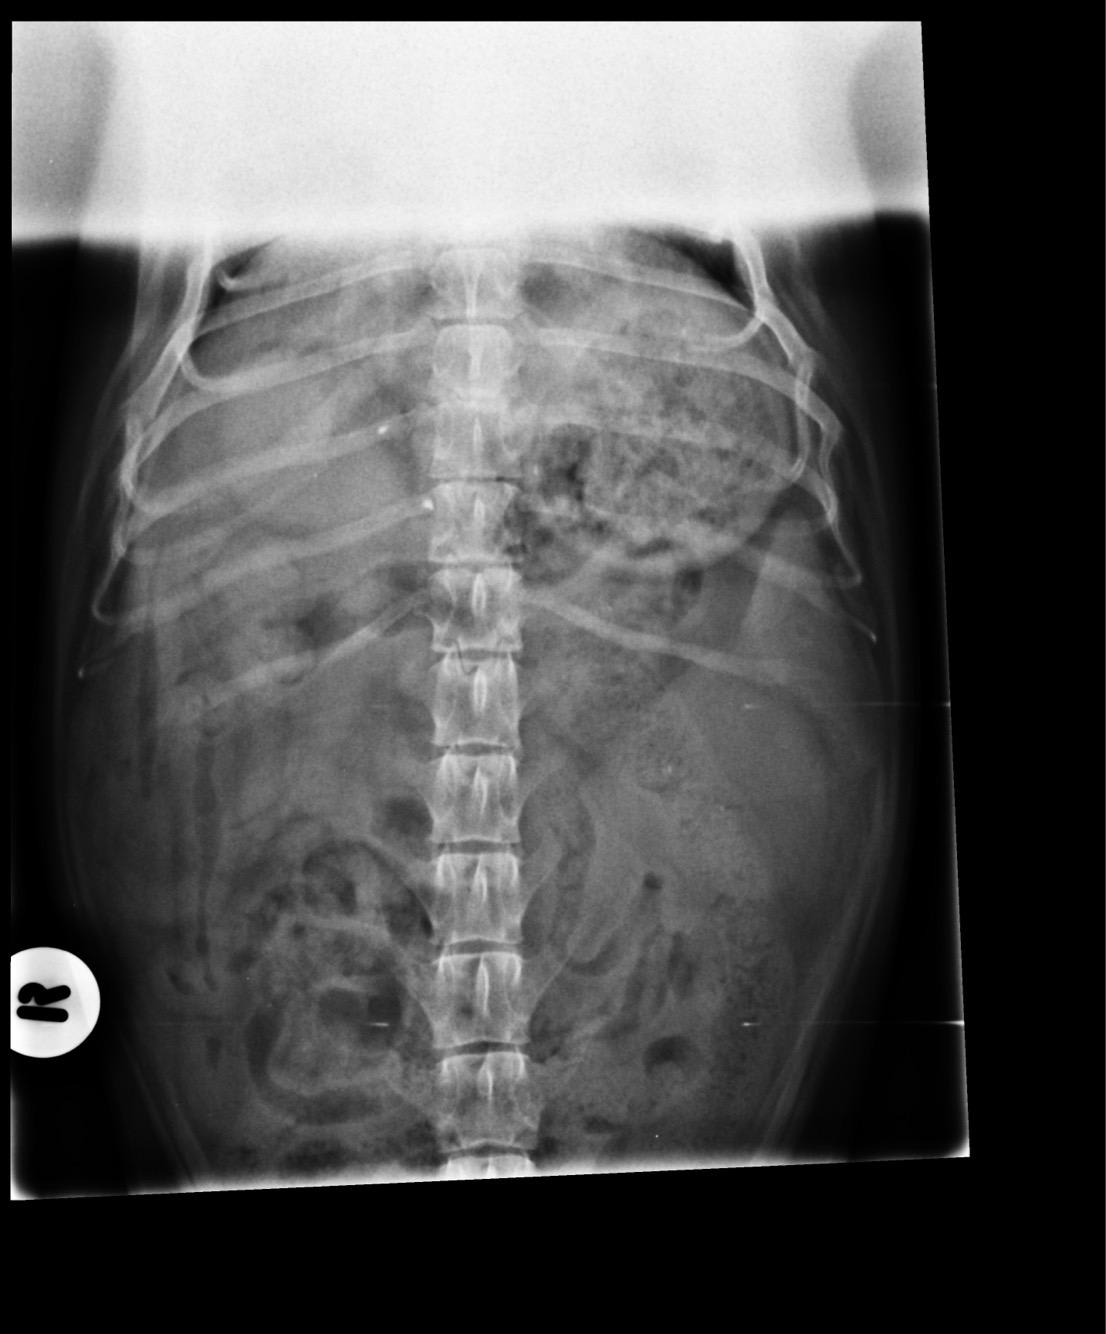

I have recently lost my dog to cancer. He had a bump on his torso on the left hand side. They did X-rays, blood tests and recommended a biopsy. We decided to opt for the biopsy, she described the bump as a bloody cavity that squirted and the results came back as attached. The bump was gone, we were instructed to give him metacam and watch if it returned. It returned 5 weeks later and was diagnosed sarcoma, but it was too late to remove. I want to know if a scan or operation could have saved him?

Hi, thanks for using Petco Pet Education Center, formerly Petcoach! Poor Rolo! From the biopsy report Rolo had hemandiosarcoma which is a very aggressive cancer of the blood vessels. We most commonly see if on the liver, spleen or right atrium of the heart. By the time it has grown it has microscopically spread else where. It is a very aggressive cancer and even with chemotherapy/radiation and surgery most dogs get more or less than 6 months after diagnosis. I do not think anything else would have cured Rolo. I am very sorry for your loss.